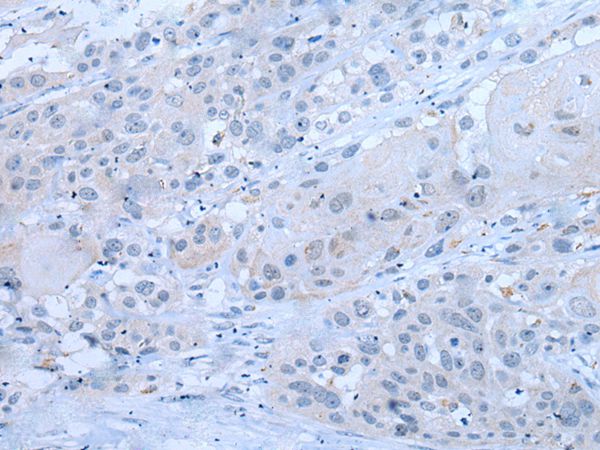

分类: 科研抗体货号: P43452别名: E2F-5应用: WB,IHC反应种属: Human,Mouse